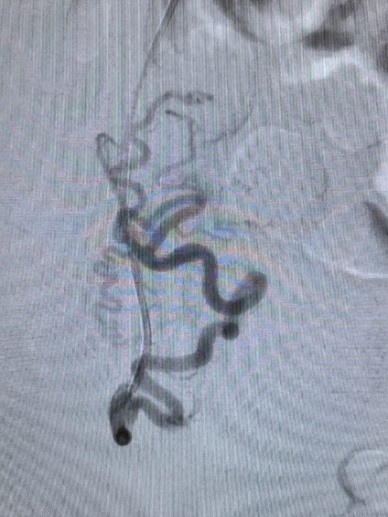

Под рентгеновским контролем определяется анатомия артерий, которые питают миоматозный узел и выполняется эмболизация – блокировка кровотока по конкретной артерии. Другие артерии малого таза, в том числе и те, которые кровоснабжают яичники остаются свободными и проходимыми.

В настоящий момент , эмболизация артерий миомы матки – самая эффективная и безопасная методика лечения миомы, которая позволяет сохранить здоровую матку.